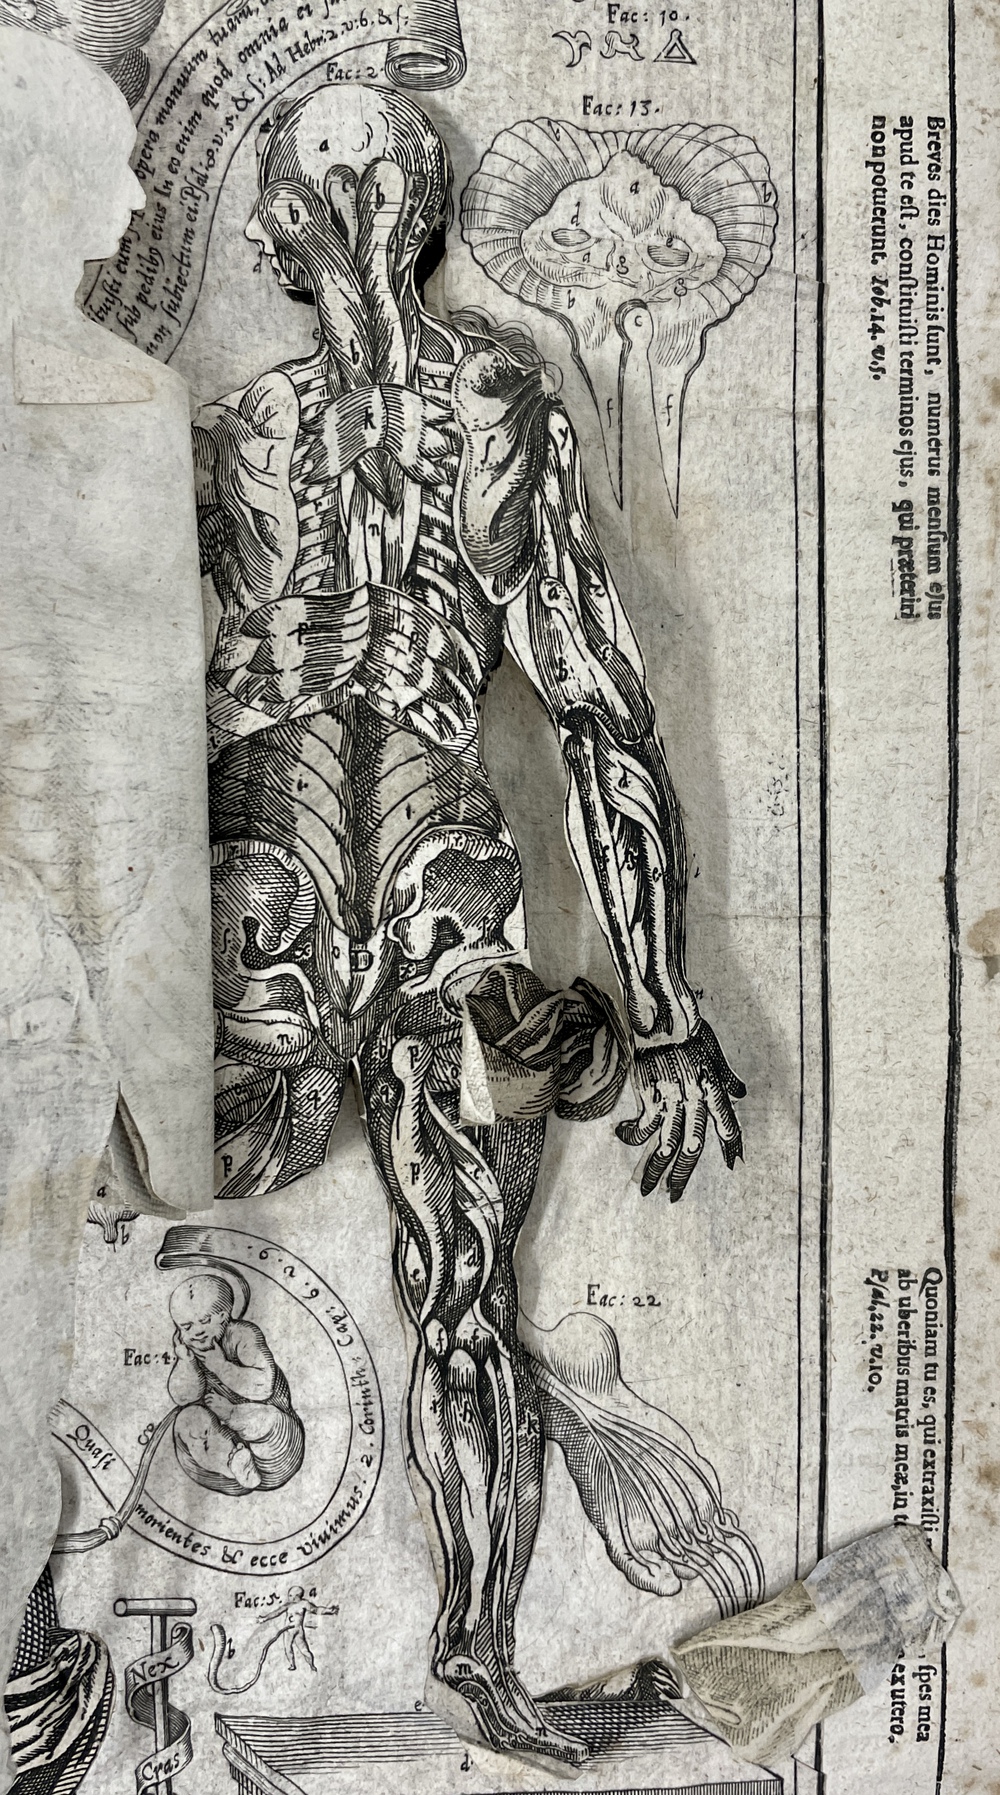

ラットの断面解剖アトラス。ラットの断面解剖アトラス - メルカリ。ラットの断面解剖アトラス。熊本県産ヒノヒカリ 30kg。 B 中古品としては綺麗と判断した商品。一般中古よりは状態の良い商品。 C 中古品として一般的な状態の商品。やや使用感があり、日焼けやキズなどがみられる場合がある商品。 D 中古品と考えても、気になる汚れやキズなどがある商品。。[A12303631]陽性・陰性症状評価尺度(PANSS)マニュアル。暫間ミニインプラント療法/永田睦(著者)。[A11078446]新生児学テキスト [単行本(ソフトカバー)] 一般社団法人 日本新生児成育医学会。改訂版・神経内科のスピード学習と専門医学習/泉義雄,五十棲一男【著】。[A12335451]徹底討論! ハートバルブ・カンファレンス。Ea-080/化学両方の領域 2016年4月号 Vol.32No.4 医薬ジャーナル社 2016年3月25日発行 特集:食の安全と微生物汚染 医療 医学 薬学/L1/61121。シノプティック・マテリア・メディカ 4訂/F.ヴァーミューラン(著者),RAH著(著者)。8K0098◆連続写真と動画で学ぶ 白内障手術パーフェクトマスター 基本から難症例への対処法まで 谷口重雄 ▽。[A01906937]すぐわかる小児の画像診断 改訂第2版 (画像診断別冊KEYBOOKシリーズ) [単行本] 荒木 力、 原 裕子; 野坂 俊介。IVR-手技,合併症とその対策 Interventional/石橋忠司(著者),山田章吾(著者)。眼光学 1 眼内レンズ/市川宏(著者)。[A11048022]造血器腫瘍アトラス 形態、免疫、染色体から分子細胞治療へ 谷脇 雅史、 横田 昇平; 黒田 純也。カラー図解 脳神経ペディア 「解剖」と「機能」が見える・つながる事典/渡辺雅彦(著者)。培養細胞実験ハンドブック 改訂 基本から最新の幹細胞培養法まで完全網羅!/黒木登志夫(著者),許南浩(著者)。[A01564935]病院の世紀の理論。機能性食品の作用と安全性百科/上野川修一(著者)。[A01351009]ICUブック 第4版。整形外科スタンダード手術基本手技/山本眞(著者)。H19-047 醫學博士 茂木藏之助 著 茂木外科總論 南山堂 書き込みあり。。胃 形態とその機能 第2版 形態とその機能/川井啓市(著者)。[A12326342]リウマチ・膠原病アトラス 廣畑 俊成。日経デジタルヘルス年鑑(2017)/日経デジタルヘルス。[A12090911]硬膜動静脈瘻塞栓術ハンドブック [単行本] 滝 和郎。[A11248770]一歩進んだ麻酔管理~常識は常に真実か?~ 国沢 卓之。[A12333909]睡眠とてんかん: その密接な関連性。[A12335621]バスキュラーアクセスのトラブルシューティング ─ 電子版付 ─。[A12344518]改訂第6版 救急診療指針 上巻 (上巻)。ネッター解剖学図譜 第2版/相磯貞和(著者)。[A01204523]EBMによる糖尿病経口薬の選択と適正使用。【まとめ/訳あり】緑内障 11冊セット 眼科/診療/薬物治療/ガイドブック/【2211-041】。[A12325943]不整脈 識る・診る・治す (循環器内科専門医バイブル) [単行本] 平尾見三; 小室一成。[A11760723]領域横断的がん取扱い規約。[A12325147]イラストでイメージする 小児の心エコー 第2版 (第2版)。眼科手術学/ゲオルク・アイスナー(著者),渡辺郁緒(著者)。[A12309814]診断と治療2019年増刊号。[A12357725]頭頸部がん手術ノート 輪層の外科。[A11067697]CTパターンから理解する呼吸器疾患: 所見×患者情報から導く鑑別と治療 門田 淳一。★カラーフォト皮膚病1★籏野 倫★。胸部CTの異常陰影/松原義人(著者)。[A12301703]オルソケラトロジ-・ハンドブック トッド・D.ウィンクラ-、 ロジャ-・T.ケイム; 日本オルソケラトロジ-協会。[A12343460]小児画像診断の勘ドコロNEO。DVD SPAT 頚椎・胸椎編/鹿島田忠史(著者)。[A11550186]腸疾患診療―プロセスとノウハウ。和蘭薬鏡(全) 科学書院。脳神経外科臨床マニュアル 改訂第5版/端和夫(編者),三國信啓(編者)。[A11185929]脊椎・骨盤の外傷手技のコツ&トラブルシューティング [DVD付] (OS NOW Instruction)